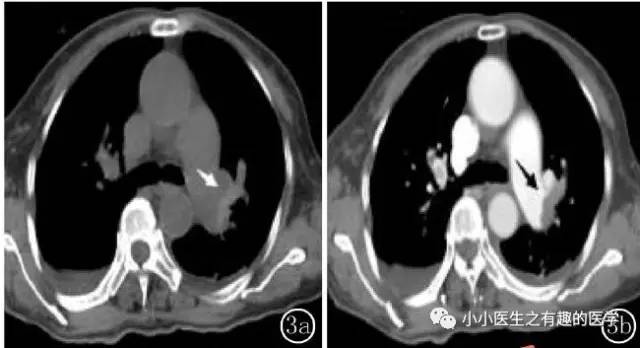

病例介绍三:

其实,我大中华也有医生用CT平扫发现可疑肺栓塞。

下面是上海交通大学的论文。

基本上看的到。